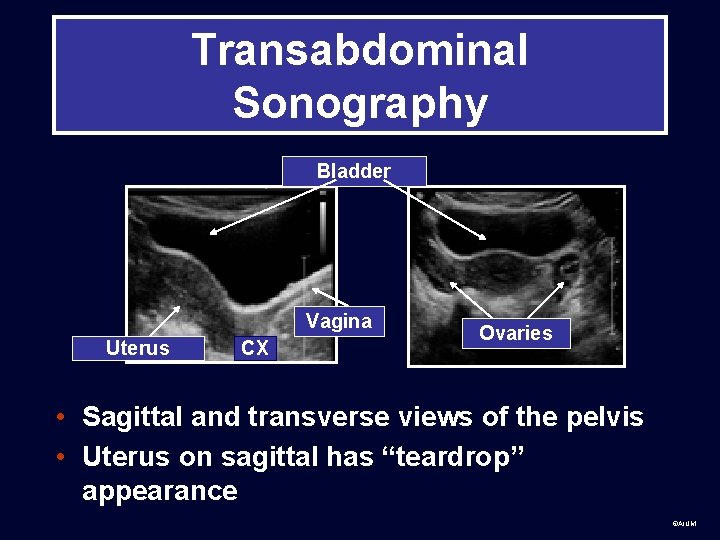

Technique • Transabdominal sonography uses a distended bladder as window to pelvic structures for a global view. ©AIUM

Transabdominal Sonography Bladder Vagina Uterus CX Ovaries • Sagittal and transverse views of the pelvis • Uterus on sagittal has “teardrop” appearance ©AIUM